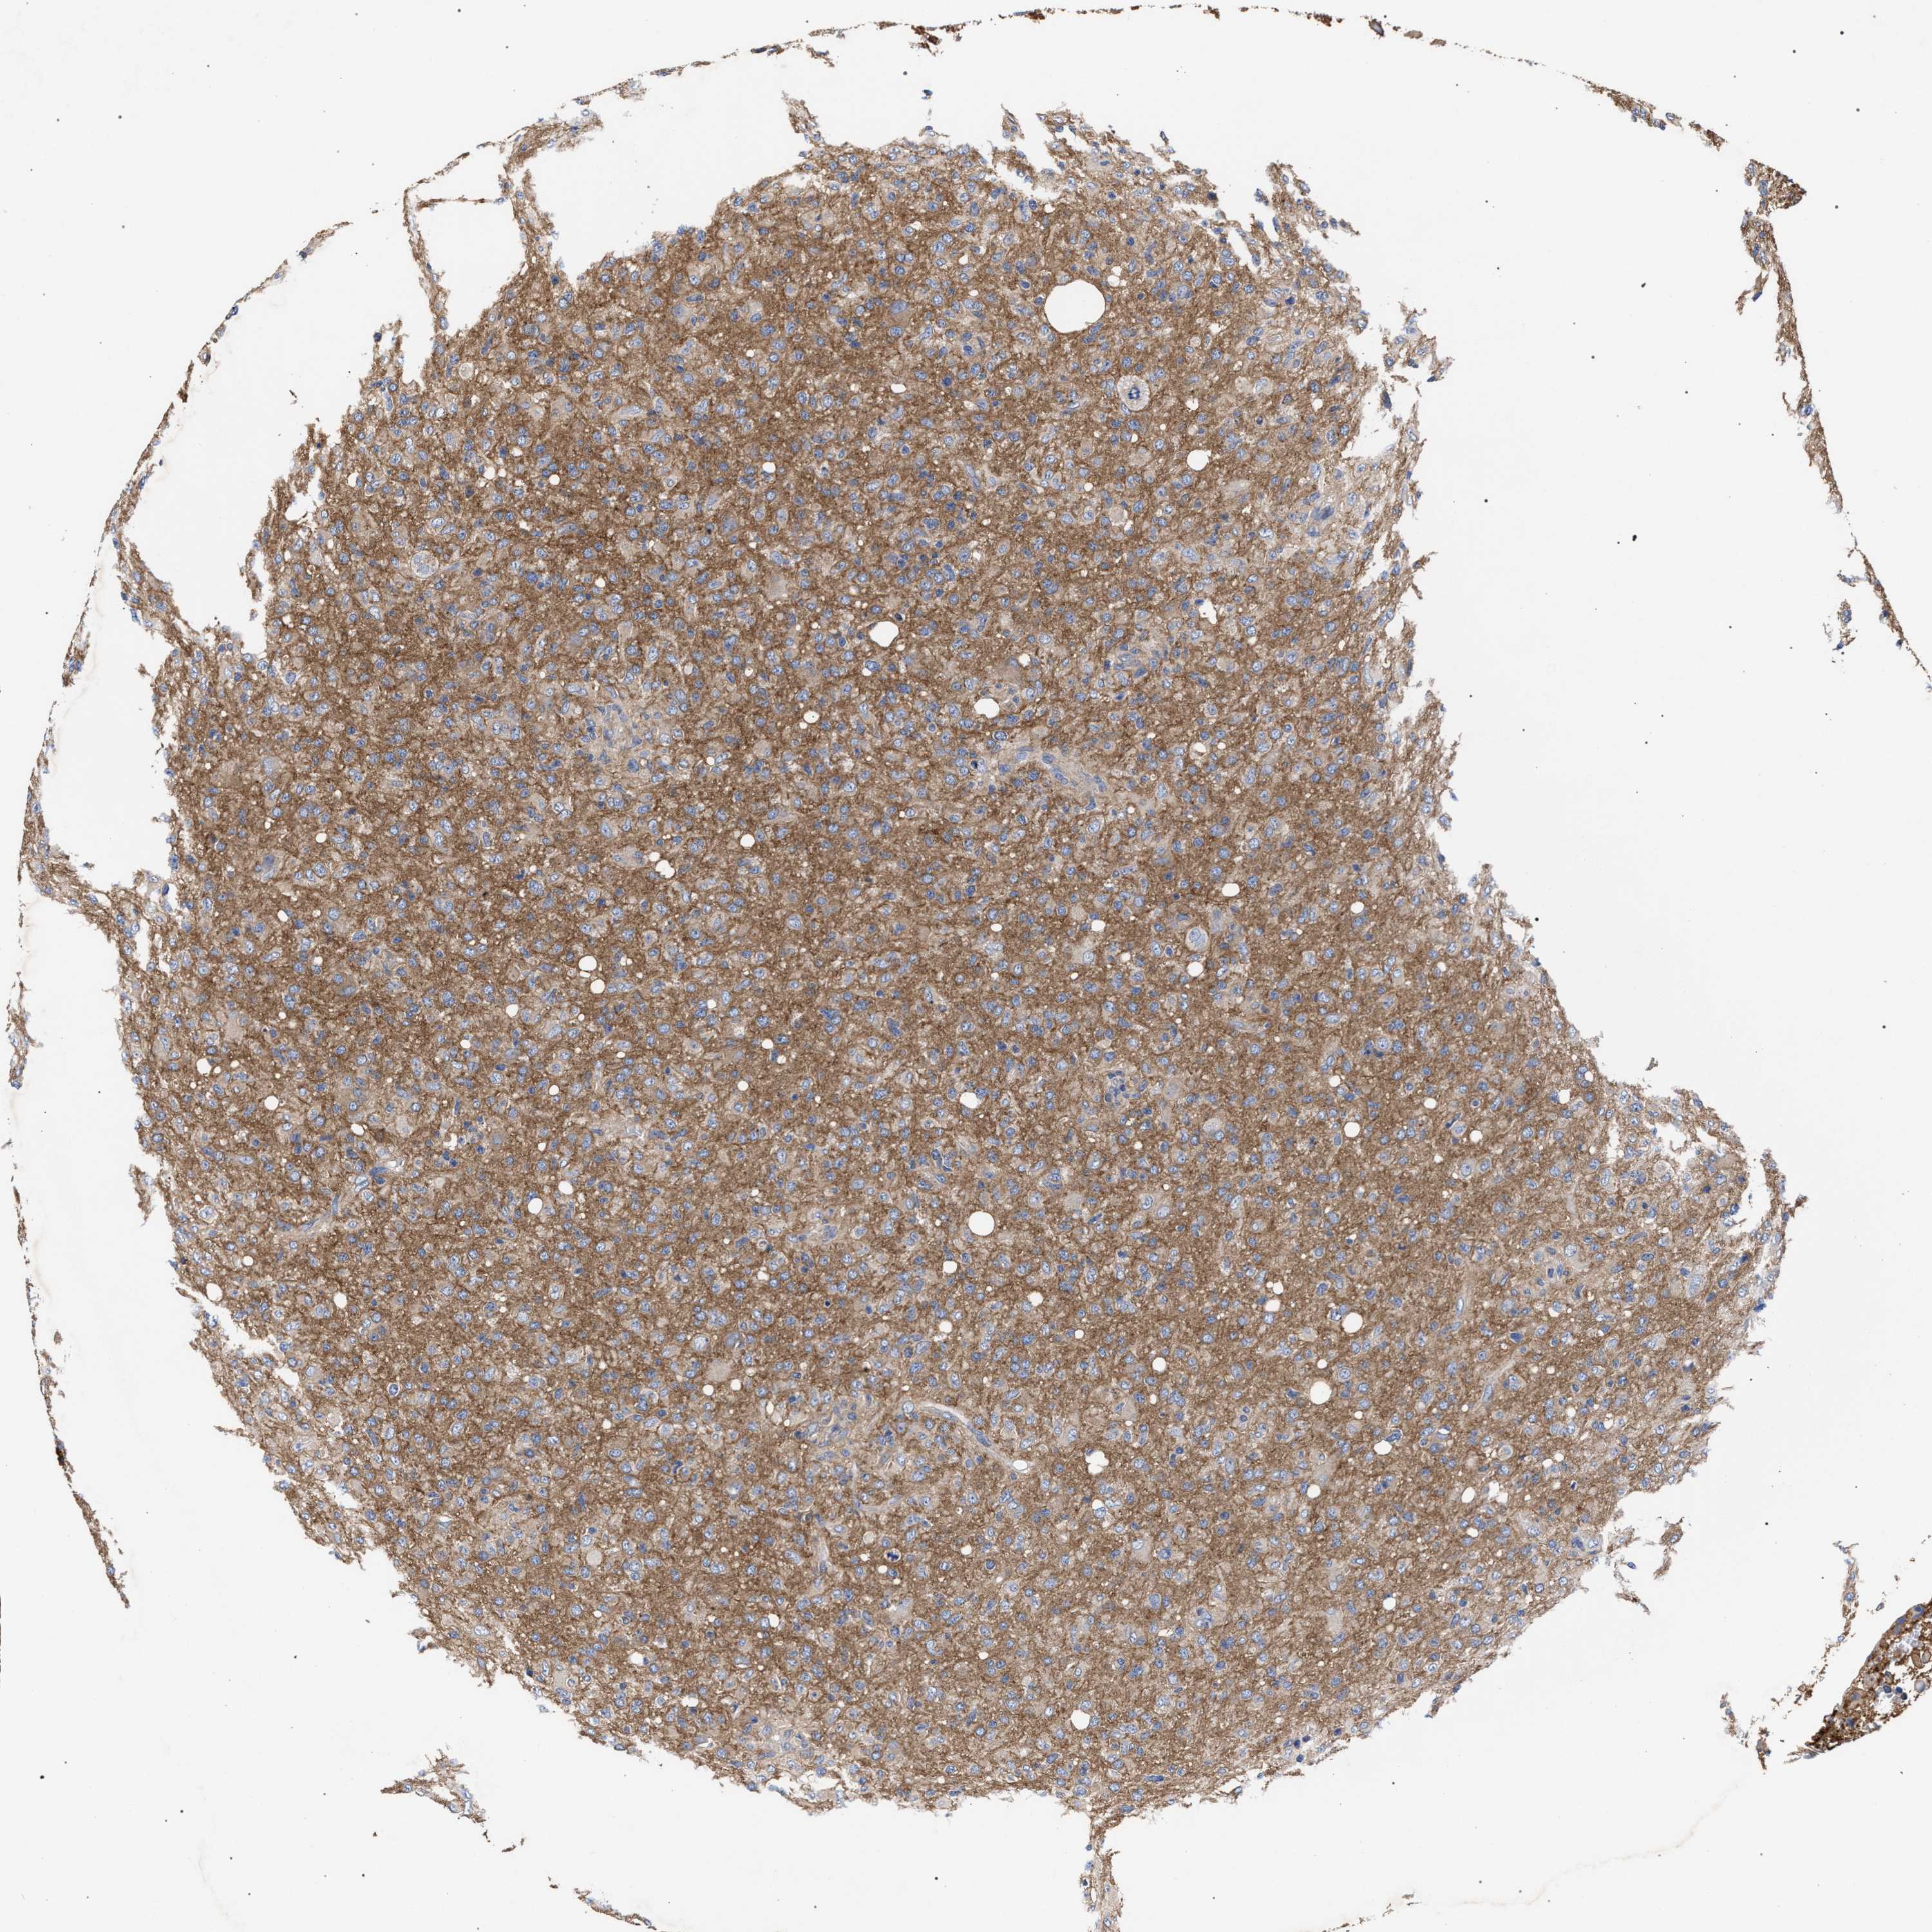

GLIOMA - Protein expressioni

A mouse-over function shows sample information and annotation data. Click on an image to view it in a full screen mode. Samples can be filtered based on level of antibody staining by selecting one or several of the following categories: high, medium, low and not detected. The assay and annotation is described here.

Antibody stainingi

Antibody staining in the annotated cell types in the current human tissue is reported as not detected, low, medium, or high, based on conventional immunohistochemistry profiling in selected tissues. This score is based on the combination of the staining intensity and fraction of stained cells.

Each image is clickable and will lead to virtual microscopy that enables deeper exploration of all samples and also displays staining intensity scores, fraction scores and subcellular localization as well as patient and tissue information for each sample.

Antibody HPA021261

Antibody HPA021325

Staining

High

Medium

Low

Not detected

Intensity

Strong

Moderate

Weak

Negative

Quantity

>75%

75%-25%

<25%

None

Location

Nuclear

Cytoplasmic/membranous

Cytoplasmic/membranous,nuclear

Glioma, malignant, High grade

Glioma, malignant, Low grade